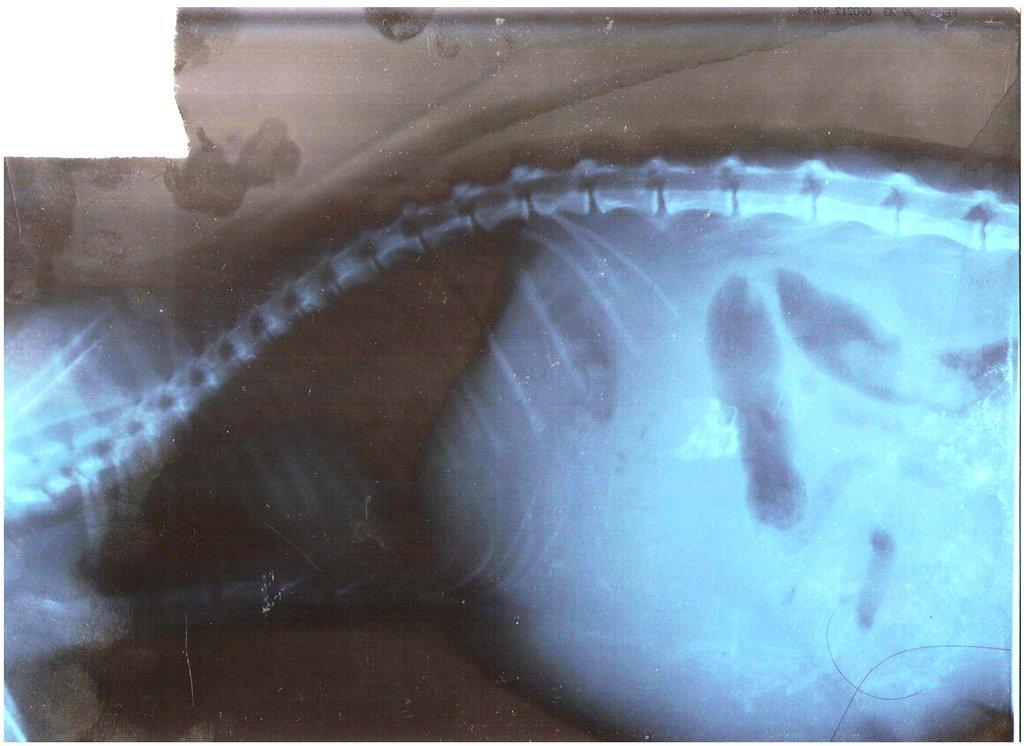

- УЗИ, рентген. Визуальное отображение состояния брюшной полости даст медику наиболее полную картину болезни.

Асцит

Еще эту болезнь называют брюшной водянкой. Характеризуется скоплением жидкости в брюшине. Провоцирующих факторов может быть несколько, в том числе нарушение работы сердца или почек. Патология требует тщательной диагностики. Внешне форма живота меняется при изменении положения тела четвероногого пациента от отвисшей до грушевидной.

Асцит называют брюшной водянкой

Инфекционный перитонит

Серьезная неизлечимая болезнь, которую провоцирует коронавирус. Зачастую под удар попадают молодые особи. Четвероногий пациент истощается, а живот увеличивается, так как в брюшине скапливается жидкость. Болевой синдром может длиться недели. Заболевание продолжается месяц или год вплоть до гибели животного. Основным признаком болезни является вздутие живота.

Перитонит

Почему у котенка большой живот, а сам худой он? Одной из самых опасных проблем, которая вызывает вздутие живота, является асцит. В этом случае котенок страдает от скапливания жидкости в брюшной полости. Перитонит очень опасен и требует немедленного врачебного вмешательства.

Как поступить, если у котенка раздулся живот? Что делать? Необходимо определить, действительно ли питомец заболел асцитом. Чтобы это сделать, рекомендуется поднять его на руки и немного подержать в вертикальном положении. Если фигура животного напоминает грушу (что происходит вследствие перетекания жидкости вниз), а после опускания живот котенка опять будет похож на шарик, то никаких сомнений быть не может. Поэтому не медлите, отправляйтесь к доктору.